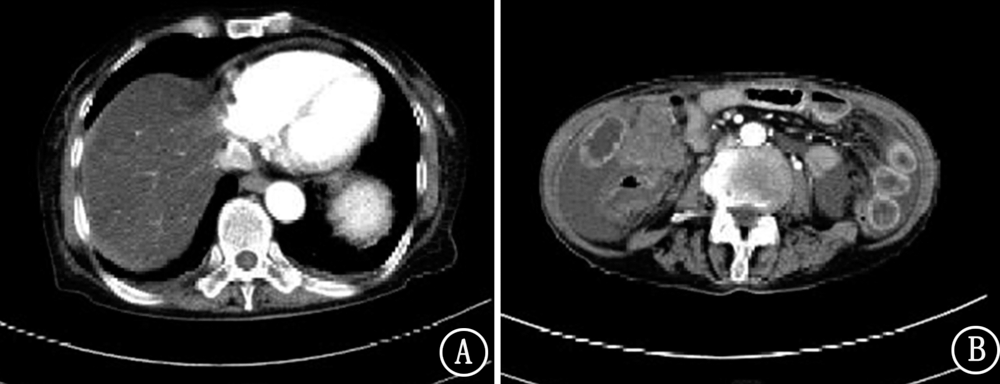

晚期胃癌目前无明确有效治疗手段,现报道1例安罗替尼治疗晚期胃癌病例,并对其临床疗效和安全性进行分析。